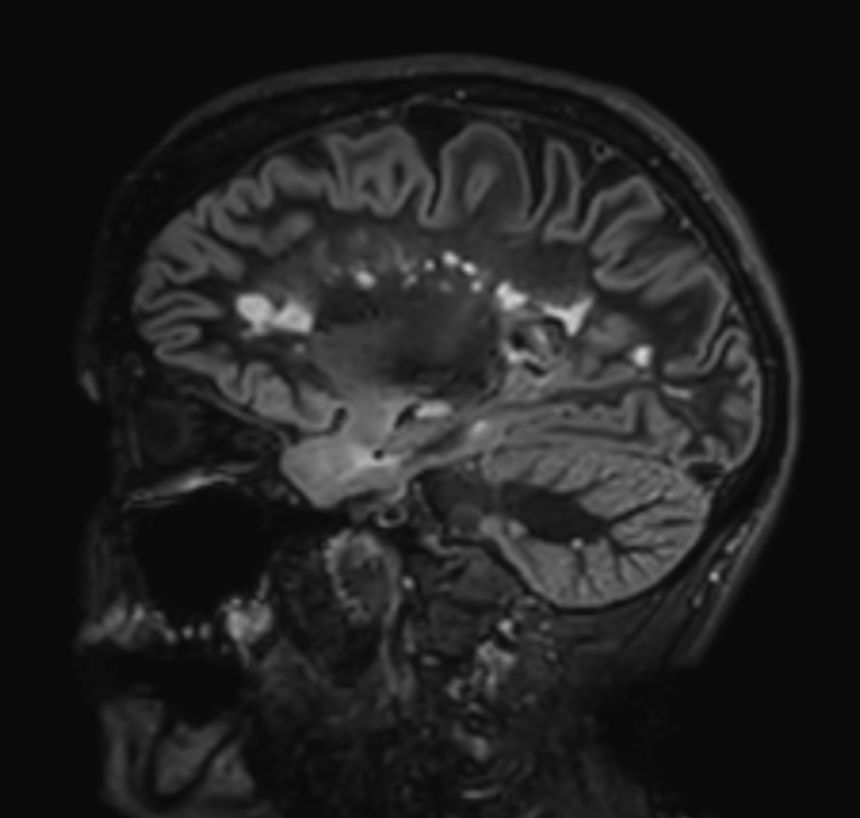

3D T2w FLAIR BrainVIEW Compressed SENSE

3D T2w FLAIR BrainVIEW (reformat) Compressed SENSE